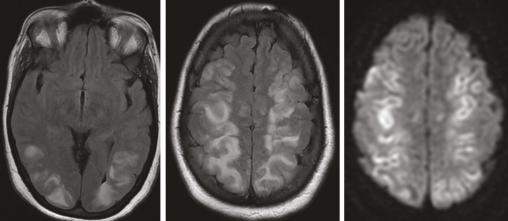

Cette femme de 36 ans avait une hypertension artérielle à 200/100 mmHg et une monoparésie du membre supérieur gauche post-critique, dans le cadre d’une toxémie gravidique. Une IRM encéphalique mettait en évidence des anomalies de signal cortico-sous-corticales et profondes, bilatérales et symétriques, prédominant aux lobes postérieurs, en iso- à hyposignal T1, hypersignal T2, Flair et diffusion avec un coefficient de diffusion apparent bas ; il n’y avait pas de prise de contraste après injection du gadolinium et pas d’anomalie de calibre des artères du polygone de Willis à l’analyse de la séquence d’angio-IRM en temps de vol (figure) . Le diagnostic était celui d’encéphalopathie postérieure probablement réversible. L’évolution était effectivement favorable, avec normalisation sous traitement de la pression artérielle. Deux mois plus tard, l’IRM montrait une disparition complète sans séquelles parenchymateuses cérébrales.

La leucoencéphalopathie postérieure réversible est une entité clinico-radiologique récemment individualisée.1 Les facteurs favorisant sa survenue sont dominés par les situations où il existe une élévation de la pression artérielle.1, 2 Les données de l’imagerie tomodensitométrique (TDM) et/ou par résonance magnétique (IRM), souvent caractéristiques, traduisent un œdème vasogénique. En TDM, l’atteinte est marquée par des hypodensités diffuses. En IRM, les lésions apparaissent en iso- ou hyposignal T1 et hypersignal T2 et Flair. L’imagerie de diffusion montre une augmentation du coefficient de diffusion. Il n’y a habituellement pas de rehaussement après injection de produit de contraste. Cette atteinte cortico-sous-corticale et profonde siège préférentiellement dans les régions postérieures (lobes pariétaux ou occipitaux dans 98 % des cas).3 L’évolution est généralement favorable sans séquelles sous traitement précoce et rapide visant à contrôler la pression artérielle et sa cause.4